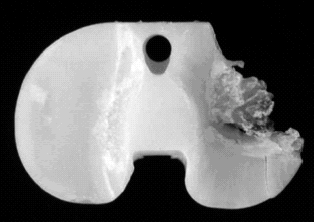

multifactorial49,50,68 (Fig. 9). The magnitude of the polyethylene problem

Retrieval studies document the severity of the wear (Fig. 9).

We now know that particulate polyethylene debris may cause osteolysis32, 37

(Fig. 10). Polyethylene particles in sufficient numbers incite a chronic

inflamma-tory process which leads to osteolysis.37 Particles of small size

(less than 15 чm) are phagocytized by

Fig. 9: Complete wear-through of a tibial polyethylene component.

Fig. 10: Large area of osteolysis caused by polyethylene wear in less than 7